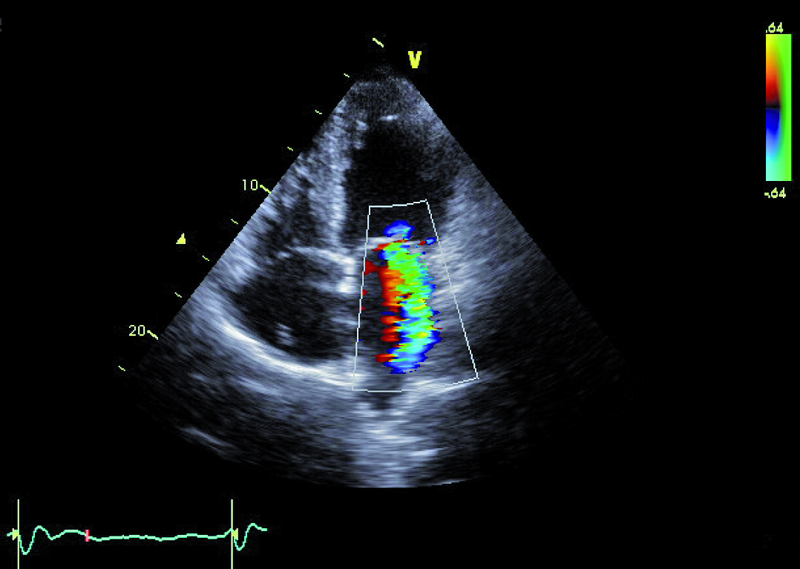

Niedomykalność zastawki mitralnej o etiologii niedokrwiennej pogarsza rokowanie u chorego z chorobą wieńcową i istotnie obniża komfort życia. Fala zwrotna w prezentowanym materiale sięga ujścia żył płucnych (ryc. 1), a ciśnienie w jamie prawej komory jest podwyższone (ryc. 2). U chorych, u których nie ma wskazań do rewaskularyzacji lub u chorych z chorobami współistniejącymi poszukuje się innych metod interwencji poza chirurgiczną naprawą. Punktem wyjścia dla rozważań o możliwości leczenia niechirurgicznego jest dokładna ocena anatomii zastawki. Wykorzystuje się dane zarówno z badania przezklatkowego, jak i przezprzełykowego, choć oczywiście optymalnym rozwiązaniem byłoby zastosowanie obrazowania trójwymiarowego. Sporo uwagi poświęca się ostatnio naprawie płatków zastawki za pomocą tzw. urządzenia mitraclip. Techniką tą można interesować się zwłaszcza w kontekście chorych bez istotnego poszerzenia pierścienia zastawki (w prezentowanym przypadku średnica pierścienia nie przekraczała 35 mm), a z dostatecznie dużą ilością tkanki tworzącej jej płatki. Założeniem techniki mitraclip, przypominającej zabieg chirurgiczny Alfieriego, jest połączenie segmentów środkowych płatka przedniego i tylnego. Skutecznie wykonany zabieg poprawia koaptację płatków i zapoczątkowuje odwrotny remodeling lewej komory, zmniejszający z kolei udział tzw. sił pociągających. Na co trzeba zwrócić uwagę, oceniając pacjenta z niedomykalnością mitralną, towarzyszącą chorobie niedokrwiennej? Niedomykalność (wg podziału Carpentiera typ 3b) powinna rzeczywiście powstawać między segmentami A2 a P2 (ryc. 3), ponieważ tylko w takim wypadku połączenie płatków i wytworzenie dwóch osobnych ujść może choremu przynieść korzyść. Ważnym elementem oceny jest uzyskanie projekcji przezżołądkowej poprzecznej. Ta projekcja bardzo dobrze ilustruje wielkość płatków i ich wzajemną relację (ryc. 4 – większy płatek tylny znajduje się bliżej głowicy). Przeciwwskazaniami do zabiegu implantacji mitraclip może być nadmierna grubość płatków, utrudniająca ich uchwycenie przez ramiona urządzenia, mniejsza niż 2 mm długość koaptacji oraz większa niż 11 mm głębokość koaptacji w stosunku do linii podstawnej pierścienia zastawki. Wymienionych cech nie potwierdzono w badaniu (ryc. 5, 6) i zakwalifikowano chorego do zabiegu w trybie planowym. Warto pamiętać, że echokardiografia służy nie tylko ocenie wskazań do zabiegu, ale stanowi także podstawę jego monitorowania.